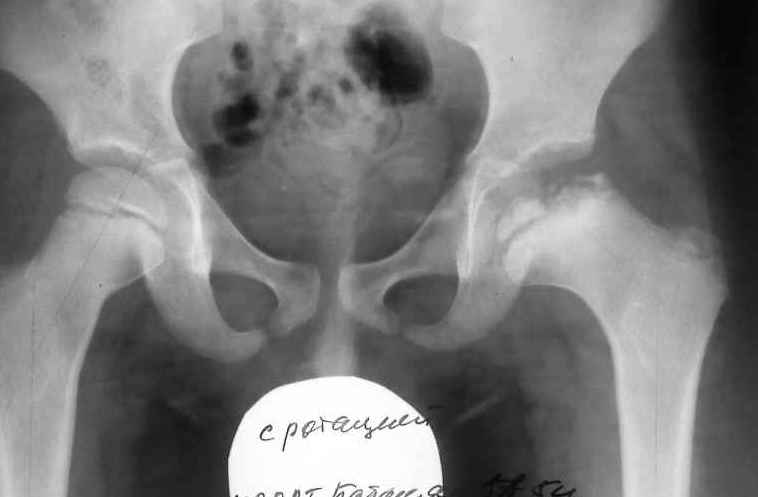

Ребёнок 5 лет заболел в июне текущего года

когда появились боли в области левого коленного сустава. Обратились за помощью к кардио-ревматологу по месту жительства. Получал консервативное лечение по поводу артрита левого коленного сустава. В июле осмотрен ортопедом , поставлен диагноз – остеохондропатия головки левого бедра - болезнь Пертеса 4-5 ст .Rg- картина представлена . Уважаемые коллеги ! Дайте совет , какой способ лечения необходим данному пациенту. Есть мысль- выполнить подвертельную деторсионно – медиализирующую остеотомию проксимального отдела бедра.

На вашей стадии заболевание формируется симптом выдавливания наружного полюса головки, ремоделяция головки в таком положение приведет к формированию подвывиха и как следствию нестабильности тазобедренного сустава с преспективой развития деформирующего коксартроза в подростково-юношеском периоде. В данном случае для ускорения процесов востановления головки и профилактики подвывиха показано малоинвазивное оперативное лечение: черезкожная алобиостимуляция головки и шейки бедра аллотрансплантатом через прокол в коже. С наложением гипсовой повязки в положение Ланге.

Ув. Вячеслав!Стандарт прогнозирования : задняя + Лауенштейн (фальшлатеральная рентгенография т\б). Используя для прогноза только заднюю рентгенографию: 5 лет + группа B за Herring ( объем поражения :lateral pillar classification) прогнозируемый исход класс А: сферическая конгруэнтность (Stulberg). Переведя на человеческий язык: консервативное лечение: разгрузка. Сontaiment не показан. Латеральной экструзии (феномена hinge abduction - шарнирного отведения) не предвидеться. По рентгенограмме видно, что движения в суставе сохранены : малый вертел "спрятан" - то есть, сохранена внутренняя ротация. Планируемое начало нагрузки через 4 -6 мес., не надо ждать полного восстановления, должен оссифицироваться латеральный столб головки. С ув. Филипчук.